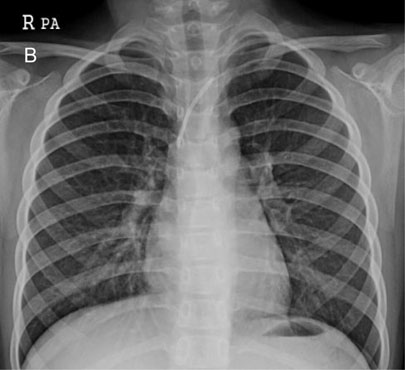

Fig. 2-A

TIVD inserted through left IJV before a removal operation.

Fig. 2-A TIVD inserted through left IJV before a removal operation.